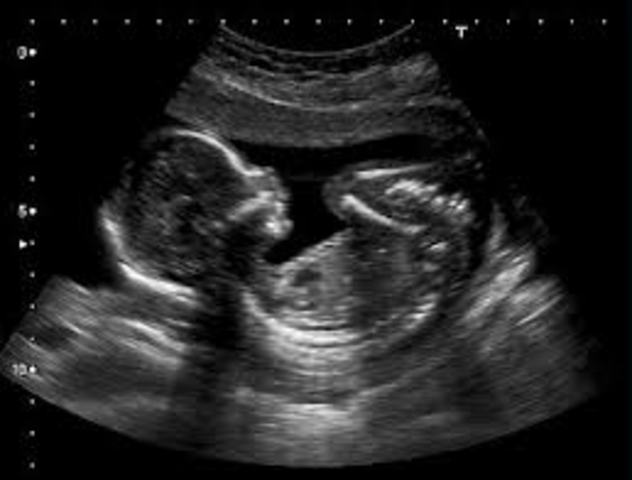

• Week 24

Week 24

Being a foot long, the baby cuts a pretty lean figure at this point, but the body is filling out proportionally and the baby soon start to plump up. the top of your uterus has risen above your belly button and is now about the size of a soccer ball.